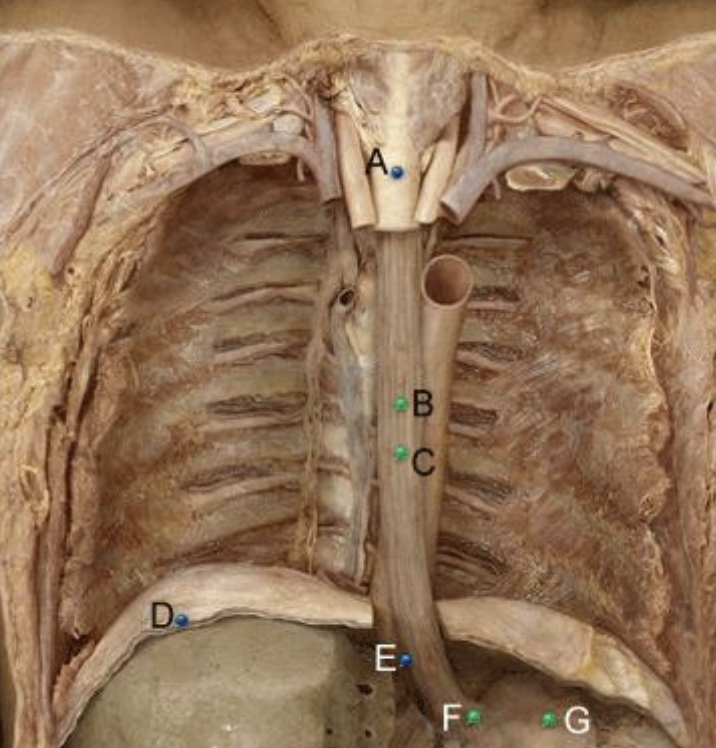

Part A?

trachea

Part B?

thoracic part of esophagus

Part C?

Esophagus

Part D?

Diaphragm

Part E?

Abdominal aorta

Part F?

abdominal part of esophagus

Part G?

Stomach